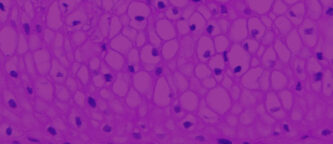

To facilitate the study of vaginal-ectocervical (VEC) toxicity, pathologies, and basic mucosal phenomena, Mattek has developed the EpiVaginal series of tissue models. EpiVaginal tissues are based on normal, human-derived VEC epithelial and dendritic cells (DC). All VEC tissues are cultured on specially prepared cell culture inserts and are multilayered and highly differentiated. The tissues closely parallel native human tissues, thus providing a useful in vitro means to assess toxicity, sexually transmitted infections, and other basic vaginal phenomena. Learn more about EpiVaginal.